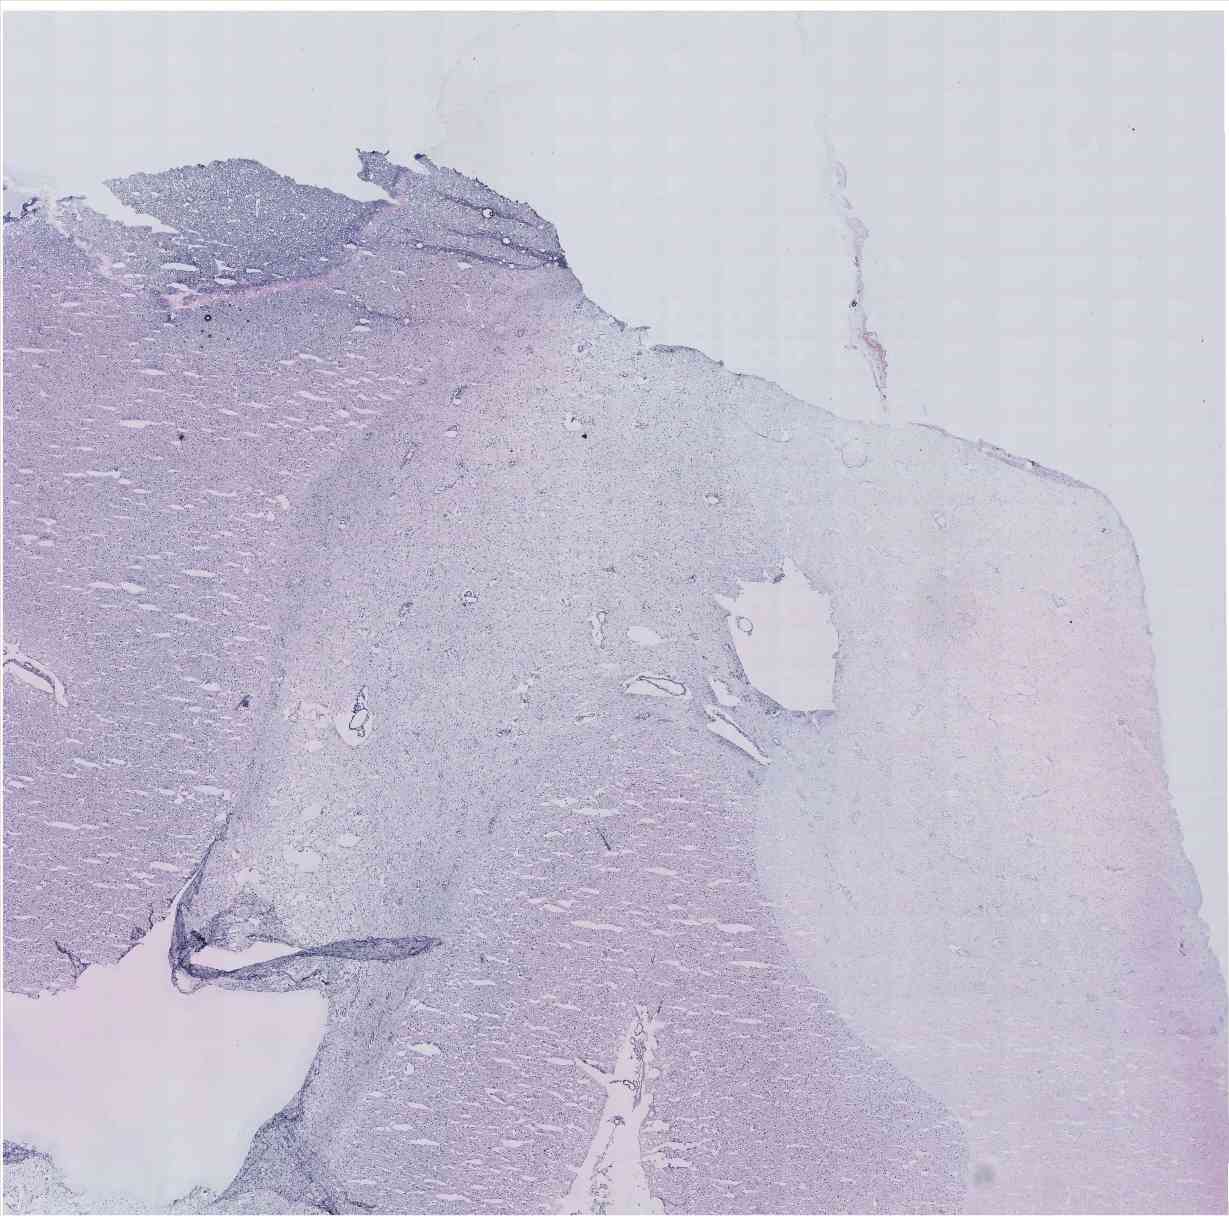

Chip 016 Well C2